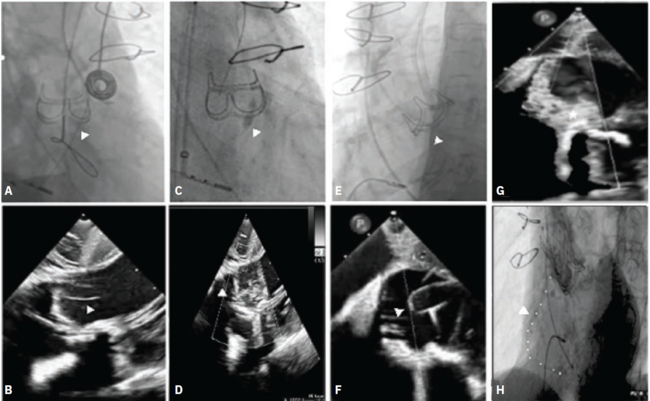

and (C, D) balloon-dilation of puncture (white arrowheads) and (E, F) leaflet laceration with “flying-V” (white arrowheads) electrocautery technique, with (G) resultant valvular aortic insufficiency on ICE (white star). (H) Aortography post-valve deployment demonstrated patent flow in RCA (white dots).

BASILICA = bioprosthetic ornative aortic scallop intentional laceration to prevent iatrogenic coronary artery obstruction during TAVR; ICE = intracardiac

echocardiography; RCA = right coronary artery; TAVR = transcatheter aortic valve replacement; ViV = valve-in-valve.

Reprinted with permission from Kodra A, Wang D, Mehla P, et al. Intracardiac echocardiography-guided leaflet modification for coronary protection prior to transcatheter valve-in-valve replacement. J Invasive Cardiol. 2024 Oct;36(10). doi: 10.25270/jic/24.00134. Copyright HMP Global.

Probably the most broadly applied of the catheter- based electrosurgeries is the BASILICA procedure; certainly, many TAVR operators are familiar with it and it has become fairly advanced. The BASILICA procedure is typically done to prepare a surgically implanted valve, although it could be a transcatheter valve, for the placement of an additional transcatheter valve (or a valve-in-valve procedure) (Figure). If the new valve is going to sit inside the old valve, you often have to first open up the prosthetic leaflets in order to keep them from becoming opposed against the coronary artery and blocking coronary flow. The leaflets are sliced to prepare for another valve to go inside of them. The idea behind the BASILICA procedure is to perforate a leaflet in a specific location using both fluoroscopy and echo guidance, deliver a catheter with sort of a denuded electrical or unshielded piece of it, and then pull it back strategically and slice the leaflet. You could also balloon facilitate, which means you make a slightly bigger hole. The BASILICA can be done on one or two leaflets.